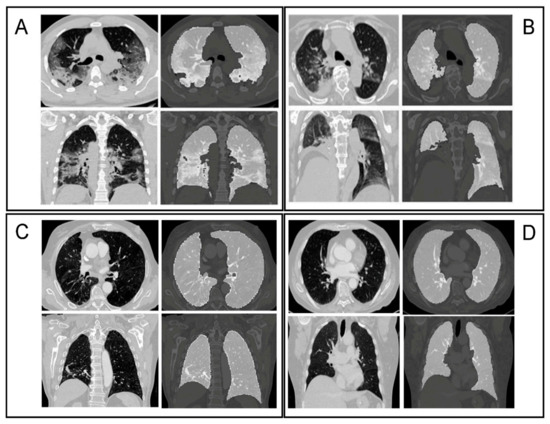

The lungs were segmented as a single structure using RadiomiX (OncoRadiomics SA, Liège, Belgium) based on Convolutional Neural Networks (CNN) by combining 2D and 3D architectures. The predicted segmentations of each architecture are assembled and the intersection constitutes the final lung segmentation which is used for extraction of radiomics features. Figure 2 shows example segmentations for four patients from both the COVID and Control groups. Complete details on the segmentation methods can be found in SI (see Appendix S1—Segmentation protocols).

Figure 2. Axial and coronal slices with accompanying segmentation masks. (A) Typical aspect of COVID-19 pneumonia characterized by bilateral multilobe ground-glass opacities of peripheral/subpleural distribution, with intralesional reticulations, presenting a “crazy paving” aspect. Subpleural atelectasis and retraction bronchiectasis, typical of organizing pneumonia can also be found; (B) a typical aspect of COVID-19 pneumonia, with posterior right lower lobe condensation and retraction of the ipsilateral diaphragm. Central and peripherical ground-glass opacities in right lower lobe, right upper lobe and left upper lobe; (C) typical chronic obstructive pulmonary disease (COPD) chest computed tomography (CT) characterized by severe centrilobular and para-septal emphysema, associated with cylindrical bronchiectasis and bronchial walls thickening. Right peripherical upper lobe tree in bud pattern seen in bronchiolitis. Middle lobe crescent-shaped atelectasis condensation; (D) normal chest CT.